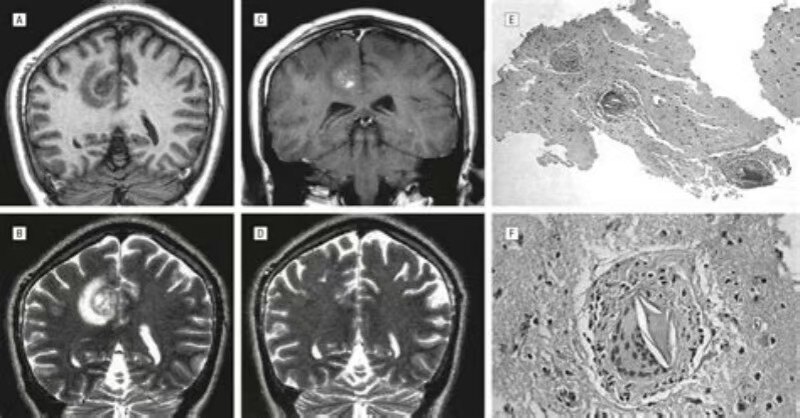

本病临床上可分为急性和慢性两型,均多见于年轻人。急性型多在感染后6个月左右发病,表现为脑膜脑炎症状:发热、意识障碍、瘫痪、抽搐及腱反射亢进、脑膜刺激症、锥体束征等。脑脊液检查正常或蛋白、白细胞数轻度增加。随着患者体温下降,症状可以有所缓解;慢性型多见于慢性早期血吸虫病患者,主要症状为癫痫发作,以局限性癫痫多见,也有患者以颅内压增高伴定位体征为主要表现。当虫卵引起脑部动脉栓塞等病变时,尚可出现突然的偏瘫和失语。此型患者多无发热。头颅CT扫描显示病灶常位于顶叶,亦可见于枕叶,为单侧多发性高密度结节影,其周围有脑水肿,甚至压迫侧脑室,使之变形。脑血吸虫病患者的内脏病变一般不明显,粪便检查可找到虫卵,血清免疫学检查有阳性发现。

CT平扫在急性型主要为脑水肿,于脑实质内可见大小不一、程度不等的低密度灶,无强化表现。慢性型表现为局限性肉芽肿,呈等或略高密度,有占位表现,边界不清,周边水肿,增强扫描可见病灶有强化现象。